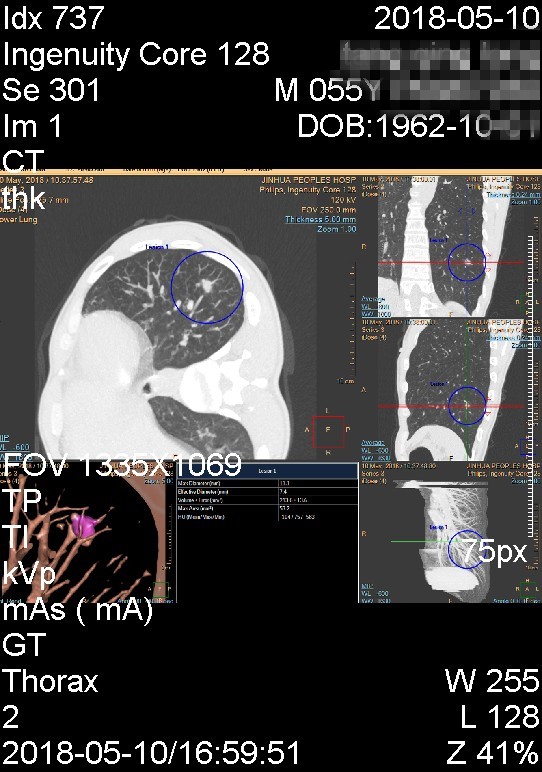

上图示重建图像结节表面略不平,总体非扁平状或片状

上图示结节为实性,有浅分叶

我们来分析患者左肺结节的特点。首先左肺下叶存在实性结节,直径约1厘米许。其次良性的主要迹象包括:1、结节边缘略显模糊;2、重建图像上看,表面不是非常粗糙,部分区域还是相对光滑;3、血管紧贴结节,不一定完全进入病灶。其中最重要的特征是边缘显模糊。第三,恶性的主要迹象包括:1、表面有浅分叶、凹凸不平;2、血管经过病灶区域受到一定程度牵拉,说明有一定的收缩性;3、上图三绝色箭头示有血管进入结节。